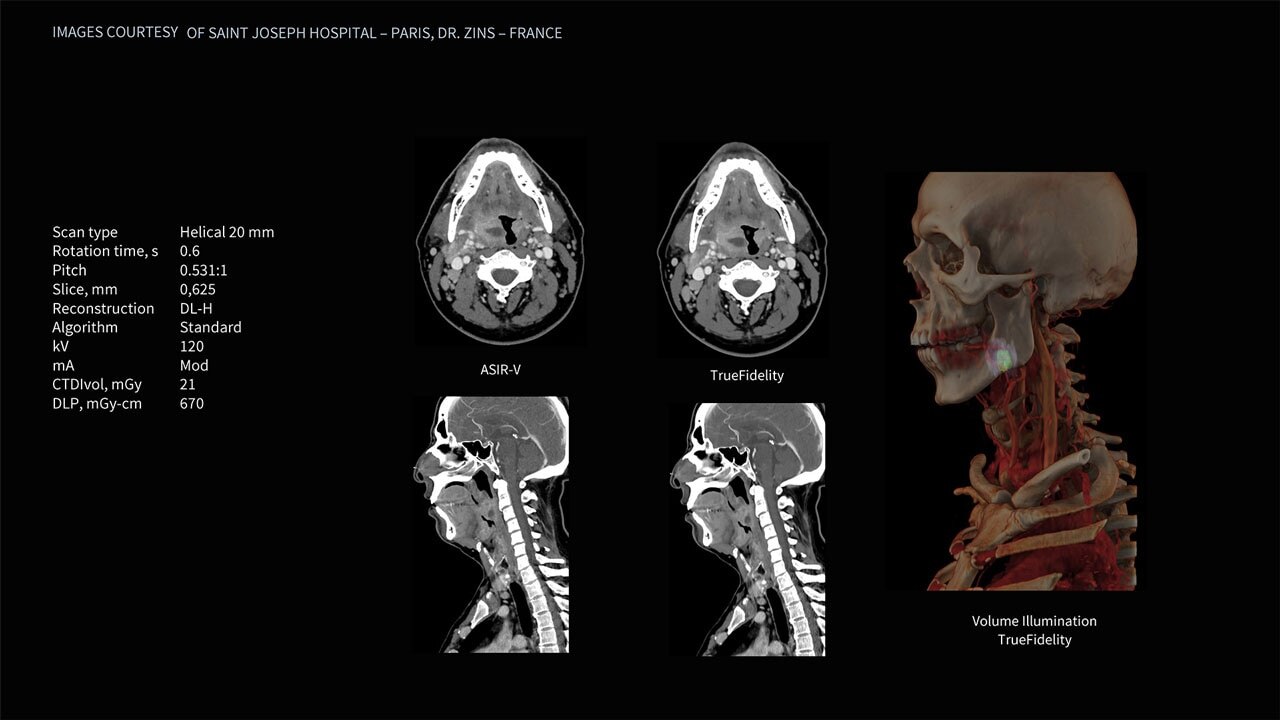

Deep learning image reconstruction, higher special resolution at 0.23 mm